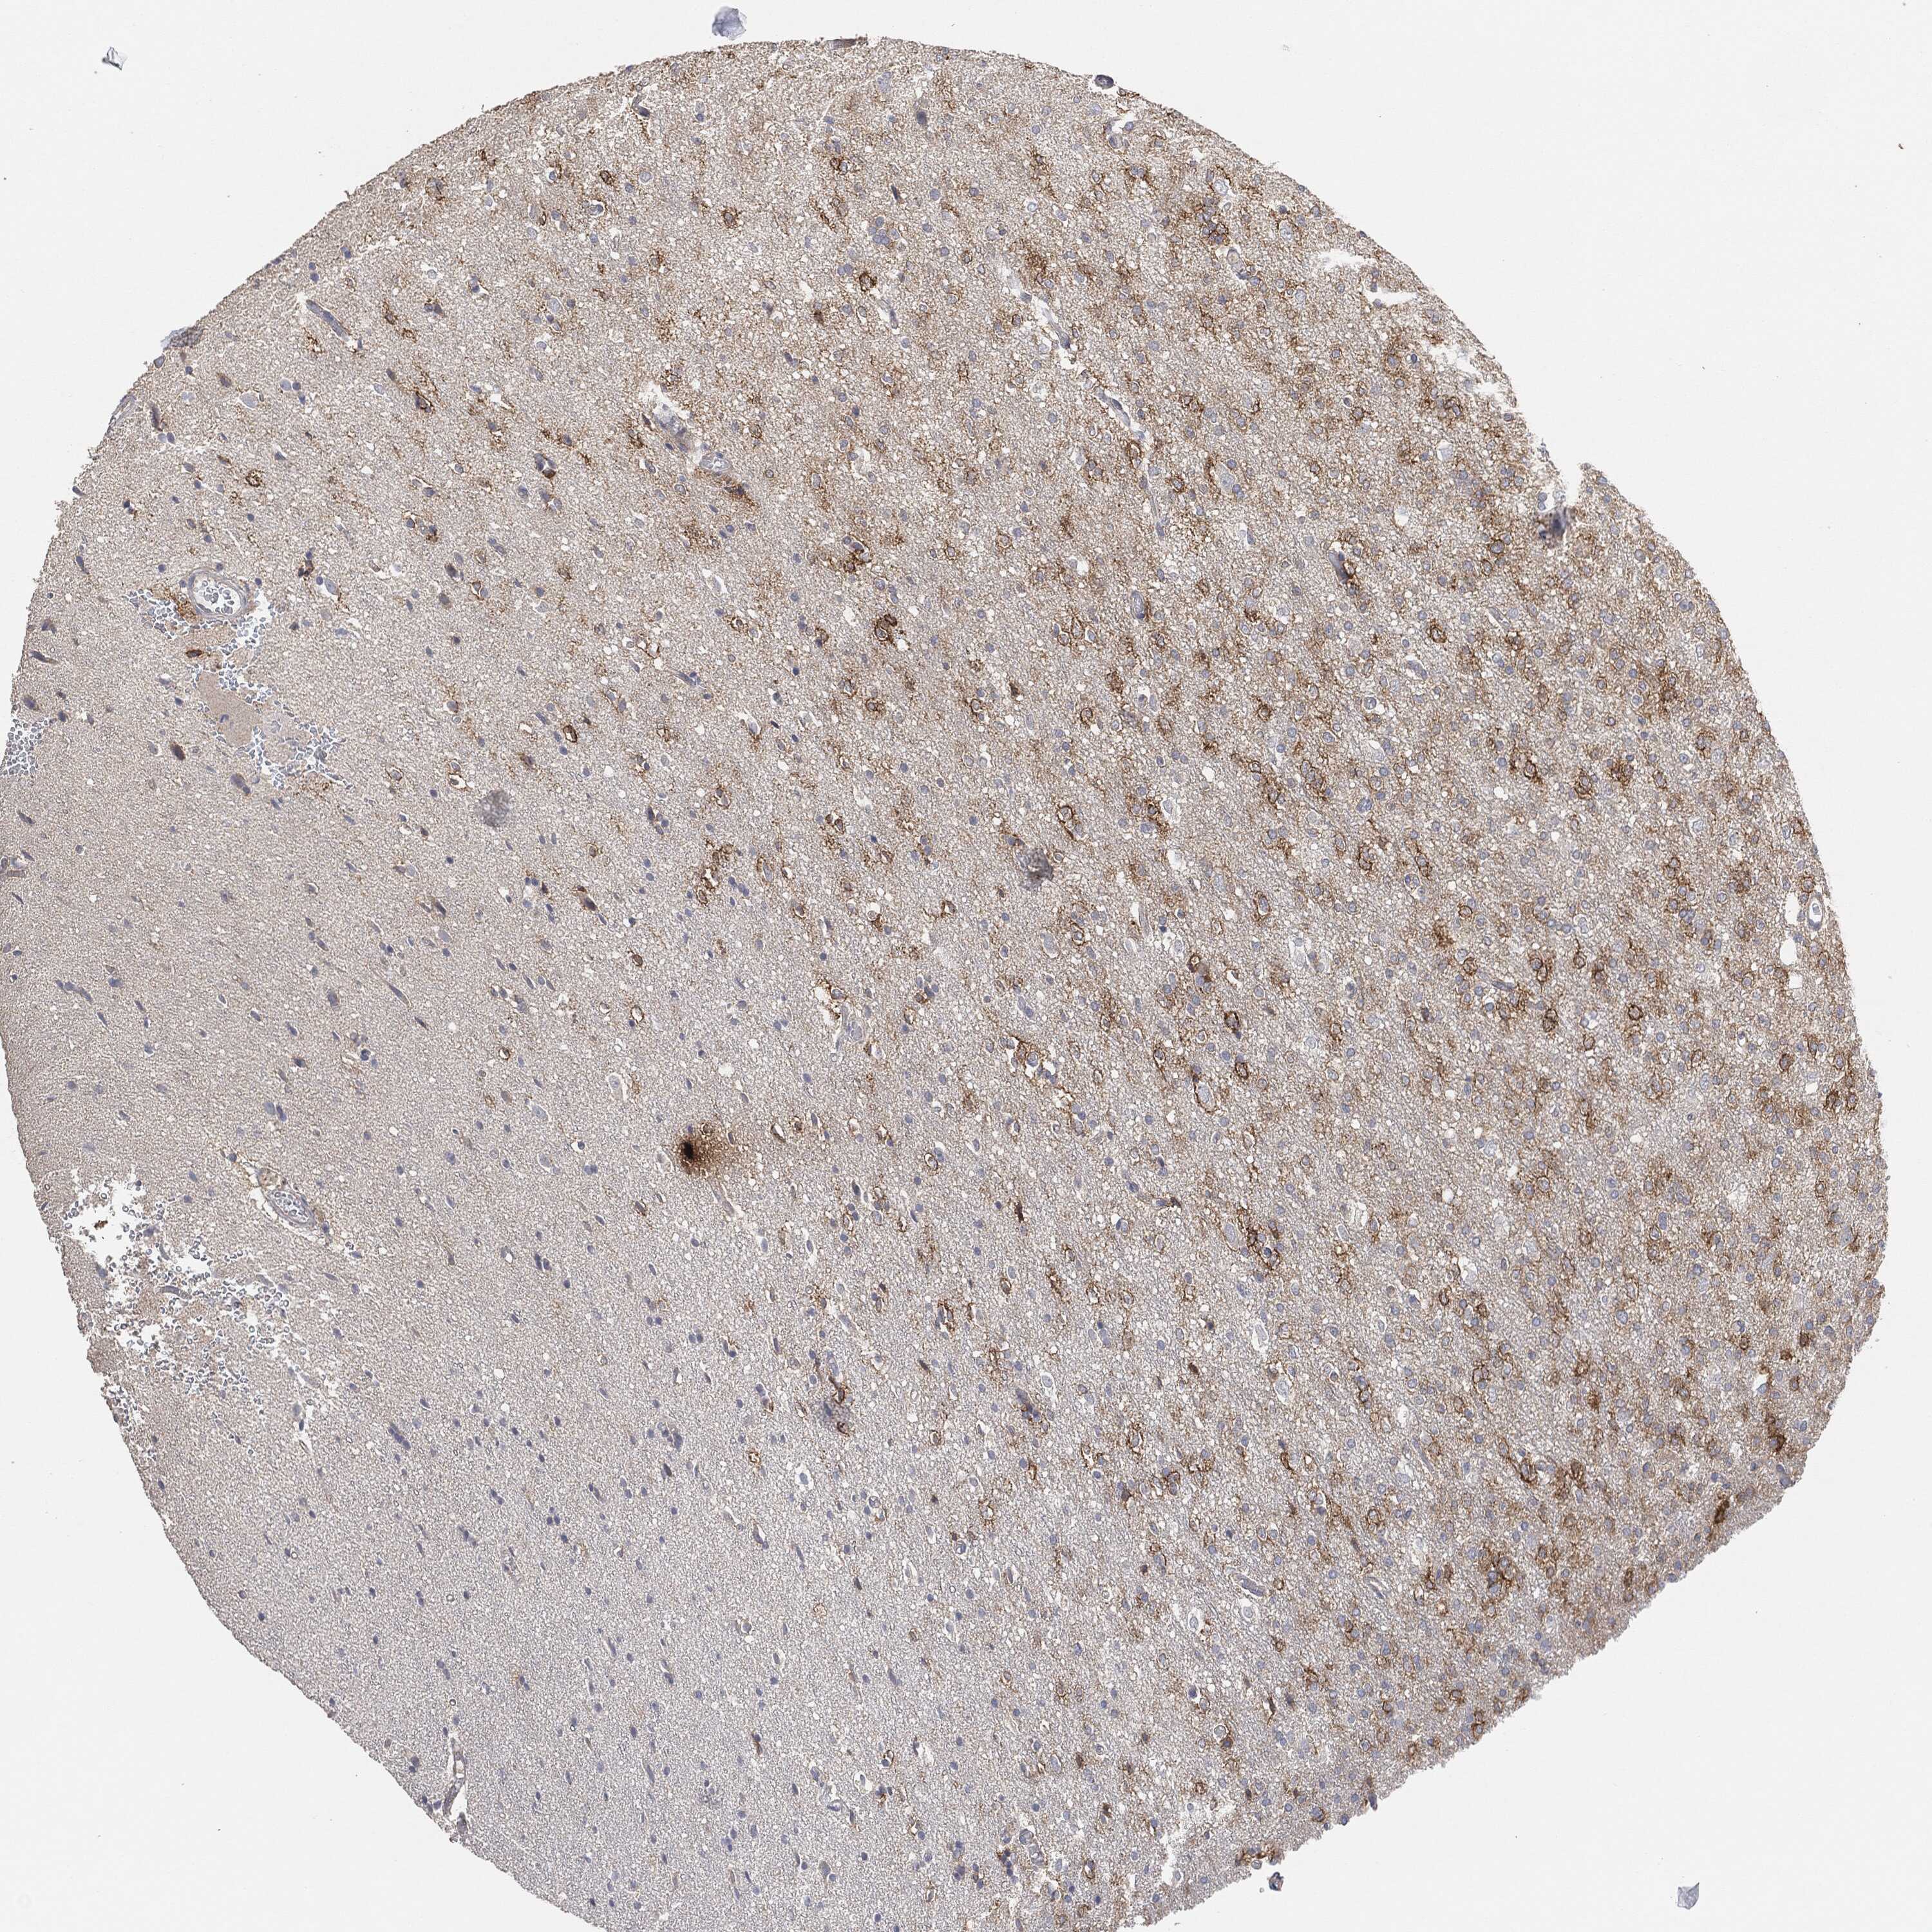

GLIOMA - Protein expressioni

A mouse-over function shows sample information and annotation data. Click on an image to view it in a full screen mode. Samples can be filtered based on level of antibody staining by selecting one or several of the following categories: high, medium, low and not detected. The assay and annotation is described here.

Note that samples used for immunohistochemistry by the Human Protein Atlas do not correspond to samples in the TCGA dataset.

Antibody stainingi

Antibody staining in the annotated cell types in the current human tissue is reported as not detected, low, medium, or high, based on conventional immunohistochemistry profiling in selected tissues. This score is based on the combination of the staining intensity and fraction of stained cells.

Each image is clickable and will lead to virtual microscopy that enables deeper exploration of all samples and also displays staining intensity scores, fraction scores and subcellular localization as well as patient and tissue information for each sample.

Glioma, malignant, High grade

Glioma, malignant, Low grade

Glioma, malignant, NOS